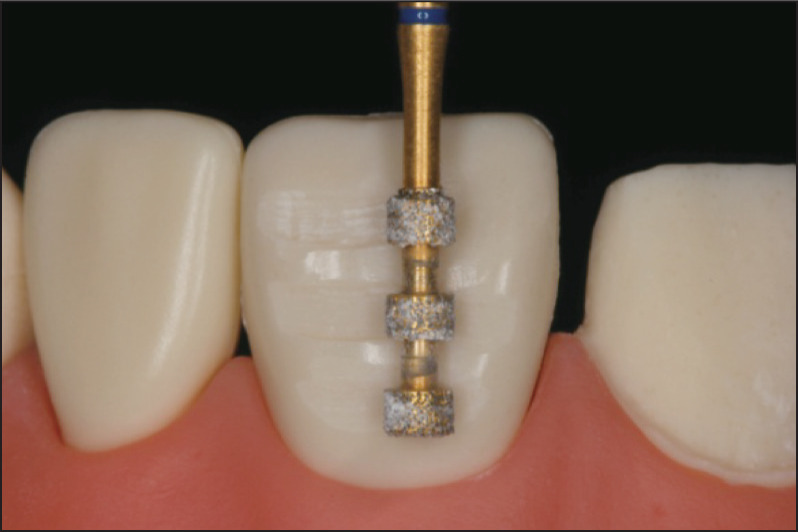

使用经验“指导”牙体预备是当前主流的牙体预备技术。早在20世纪70年代左右,在牙体表面制备定深沟指导预备的方法就被提出[16]。这种方法简便易行,实用性强,但因其仅凭医生的目测判断和临床经验确定磨除,面对需要更改突度或轴向的牙体预备手术,很容易出现预备过度或不足的情况,严重影响修复效果和患者牙体健康,是一种学习曲线长、靠经验累积且被证明预备精度低的牙体预备方法[17]–[19]。

目测经验引导的方法主要参考牙体原有表面或邻牙空间位置,难以应对目标修复空间关系复杂的ETRS、MTRS情况,虽然市场上推出了各种技术及产品试图改进其便利性与精确性,但仍难以从容应对复杂的临床情况(图2),其精准度早已无法满足百微米级实操精度的要求。

图 2. 定深沟引导的牙体预备.

Fig 2 Tooth preparation guided by depth groves